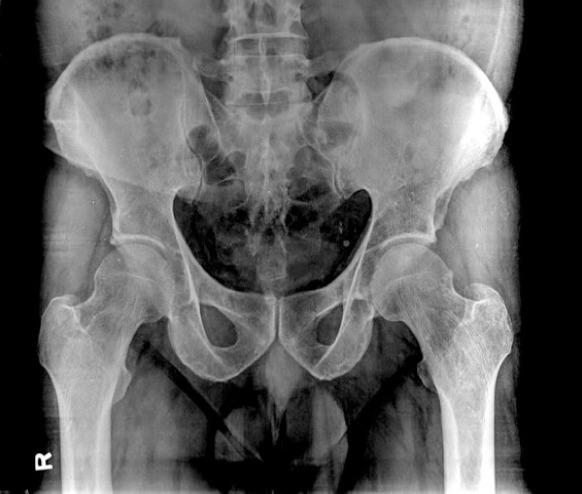

We retrospectively collected the data of patients who were diagnosed with TOH from March 2017 to March 2022. A total of 10 patients with a mean age of 43.7 years (range 33-56 years) were included in the study. The mean time to presentation from the onset of symptoms was 4 weeks (range 2-8 weeks) Radiologic evaluation with radiographs was sensitive in only 8 patients with osteopenia, whereas magnetic resonance imaging (MRI) was sensitive in all the patients and aided in early diagnosis of TOH. Radiographic evaluation alone leads to a mean delay in TTD of 1.6 weeks (range 0-8 weeks) in our study. All the patients were treated conservatively without any major complications.

我们回顾性收集了2017年3月至2022年3月期间被诊断为TOH的患者数据。共有10名患者纳入研究,平均年龄43.7岁(范围33 - 56岁)。从症状出现到就诊的平均时间为4周(范围2 - 8周)。X线平片的放射学评估仅对8名骨质减少患者敏感,而磁共振成像(MRI)对所有患者均敏感,有助于TOH的早期诊断。在我们的研究中,仅进行X线平片评估导致诊断时间平均延迟1.6周(范围0 - 8周)。所有患者均接受保守治疗,无任何重大并发症。